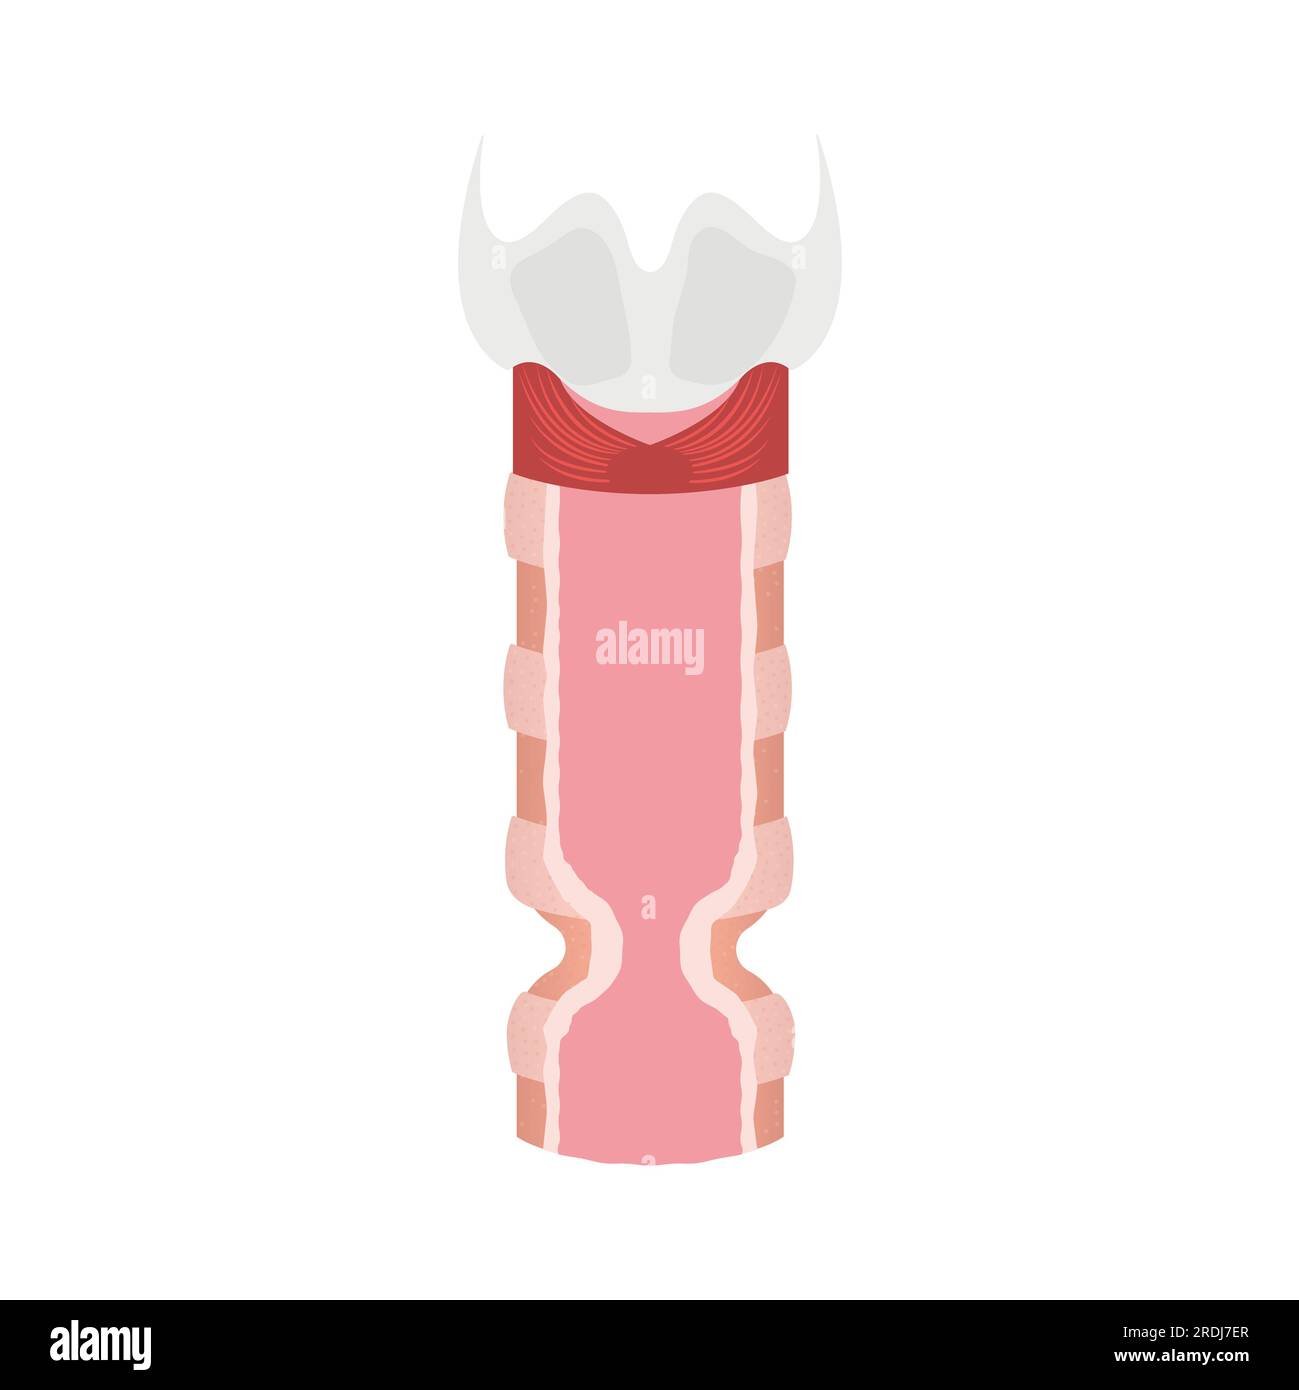

Tracheal stenosis, illustration Stock Photohttps://www.alamy.com/image-license-details/?v=1https://www.alamy.com/tracheal-stenosis-illustration-image559123343.html

Tracheal stenosis, illustration Stock Photohttps://www.alamy.com/image-license-details/?v=1https://www.alamy.com/tracheal-stenosis-illustration-image559123343.htmlRF2RDJ7ER–Tracheal stenosis, illustration